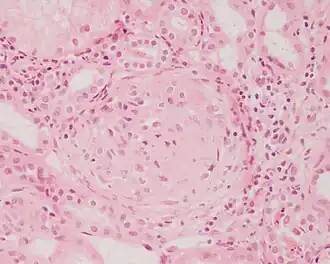

Description de l'image Crescentic glomerulonephritis HE stain.JPEG.

Une glomérulonéphrite est une affection (souvent d'origine inflammatoire) du glomérule, composante du néphron, l’unité fonctionnelle du rein. Ses manifestations affectent les deux reins de manière égale. Elle peut être asymptomatique, mais le plus souvent elle est responsable d'hématurie ou de protéinurie. La glomérulonéphrite peut être aigüe ou chronique. Les glomérulonéphrites sont le plus souvent primitives mais on peut parfois mettre en évidence des causes infectieuses (bactériennes, virales ou parasitaires), auto-immunes ou au syndrome paranéoplasique.

Le diagnostic se fait par biopsie rénale. Suivant les lésions, on parle de glomérulonéphrite extramembraneuse, de glomérulonéphrite membranoproliférative, de glomérulonéphrite segmentaire et focale de lésions glomérulaires minimes, de maladie de Berger.